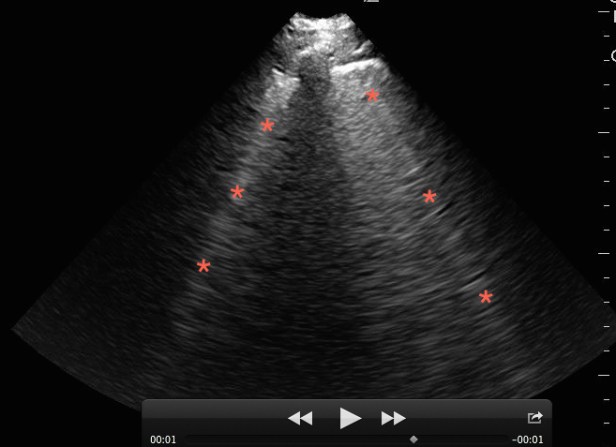

Figure 9. Lung ultrasound on a patient with pulmonary edema and B-lines (*).

B-lines are hyperechoic vertical lines that originate from the pleural line, obliterate A-lines, and often run off the bottom of the image. Three or more in the screen are indicative of interstitial syndrome. A diffuse B-line pattern in all lung segments narrows the differential to those conditions that present with a diffuse interstitial lung pattern such as pulmonary edema (cardiogenic and non-cardiogenic), multifocal pneumonia, and pulmonary fibrosis. A focal B-line pattern in one or two lung segments narrows the differential to a focal interstitial process such as pneumonia, pulmonary contusion, or pulmonary infarction.